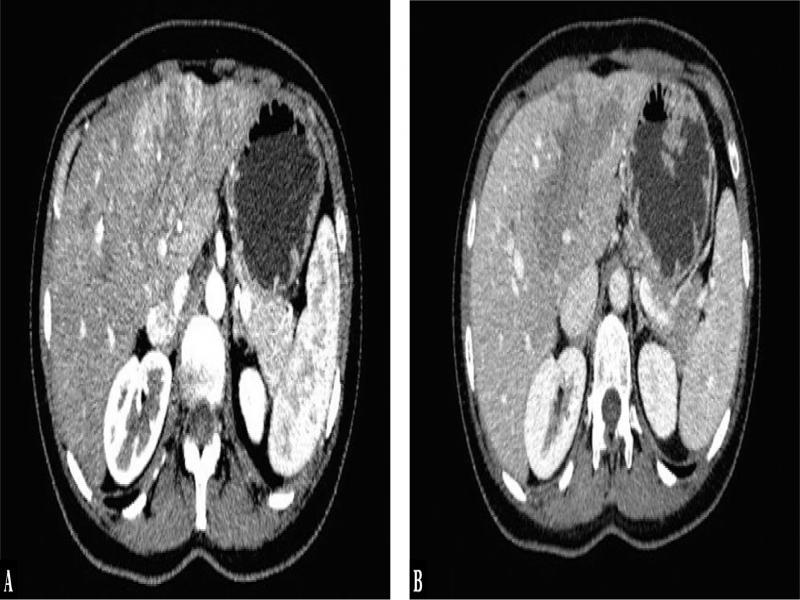

Fig. 3.

Axial contrast-enhanced CT images show streaky and heterogeneous enhancement of the PV thrombus during the late arterial phase (A) with washout during the portal venous phase (B), which is diagnostic of tumor thrombus